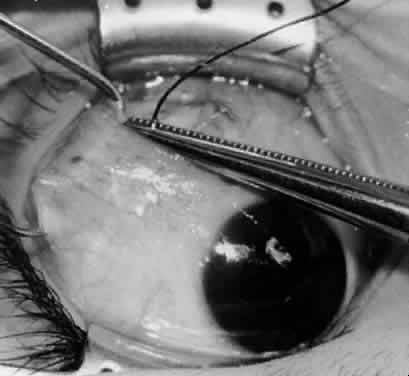

Fig. 33. A 6-0 Vicryl suture is placed in the inferior oblique muscle in preparation for anterior transposition. A Green muscle hook is placed beneath the inferior rectus muscle.

Fig. 34. The eye is retracted nasally with a Green muscle hook. The anterior suture is placed just anterior and temporal to the insertion of the inferior rectus muscle. The posterior suture is applied about 10 mm temporal to the inferior rectus muscle on a line that would be continuous with the inferior rectus insertion if it were extended temporally.

Fig. 35. The suture is tied, and the inferior oblique muscle is in the position for anterior transposition. The inferior rectus muscle is retracted nasally on the Green muscle hook, and the Desmarres lid retractor is placed inferior temporally.